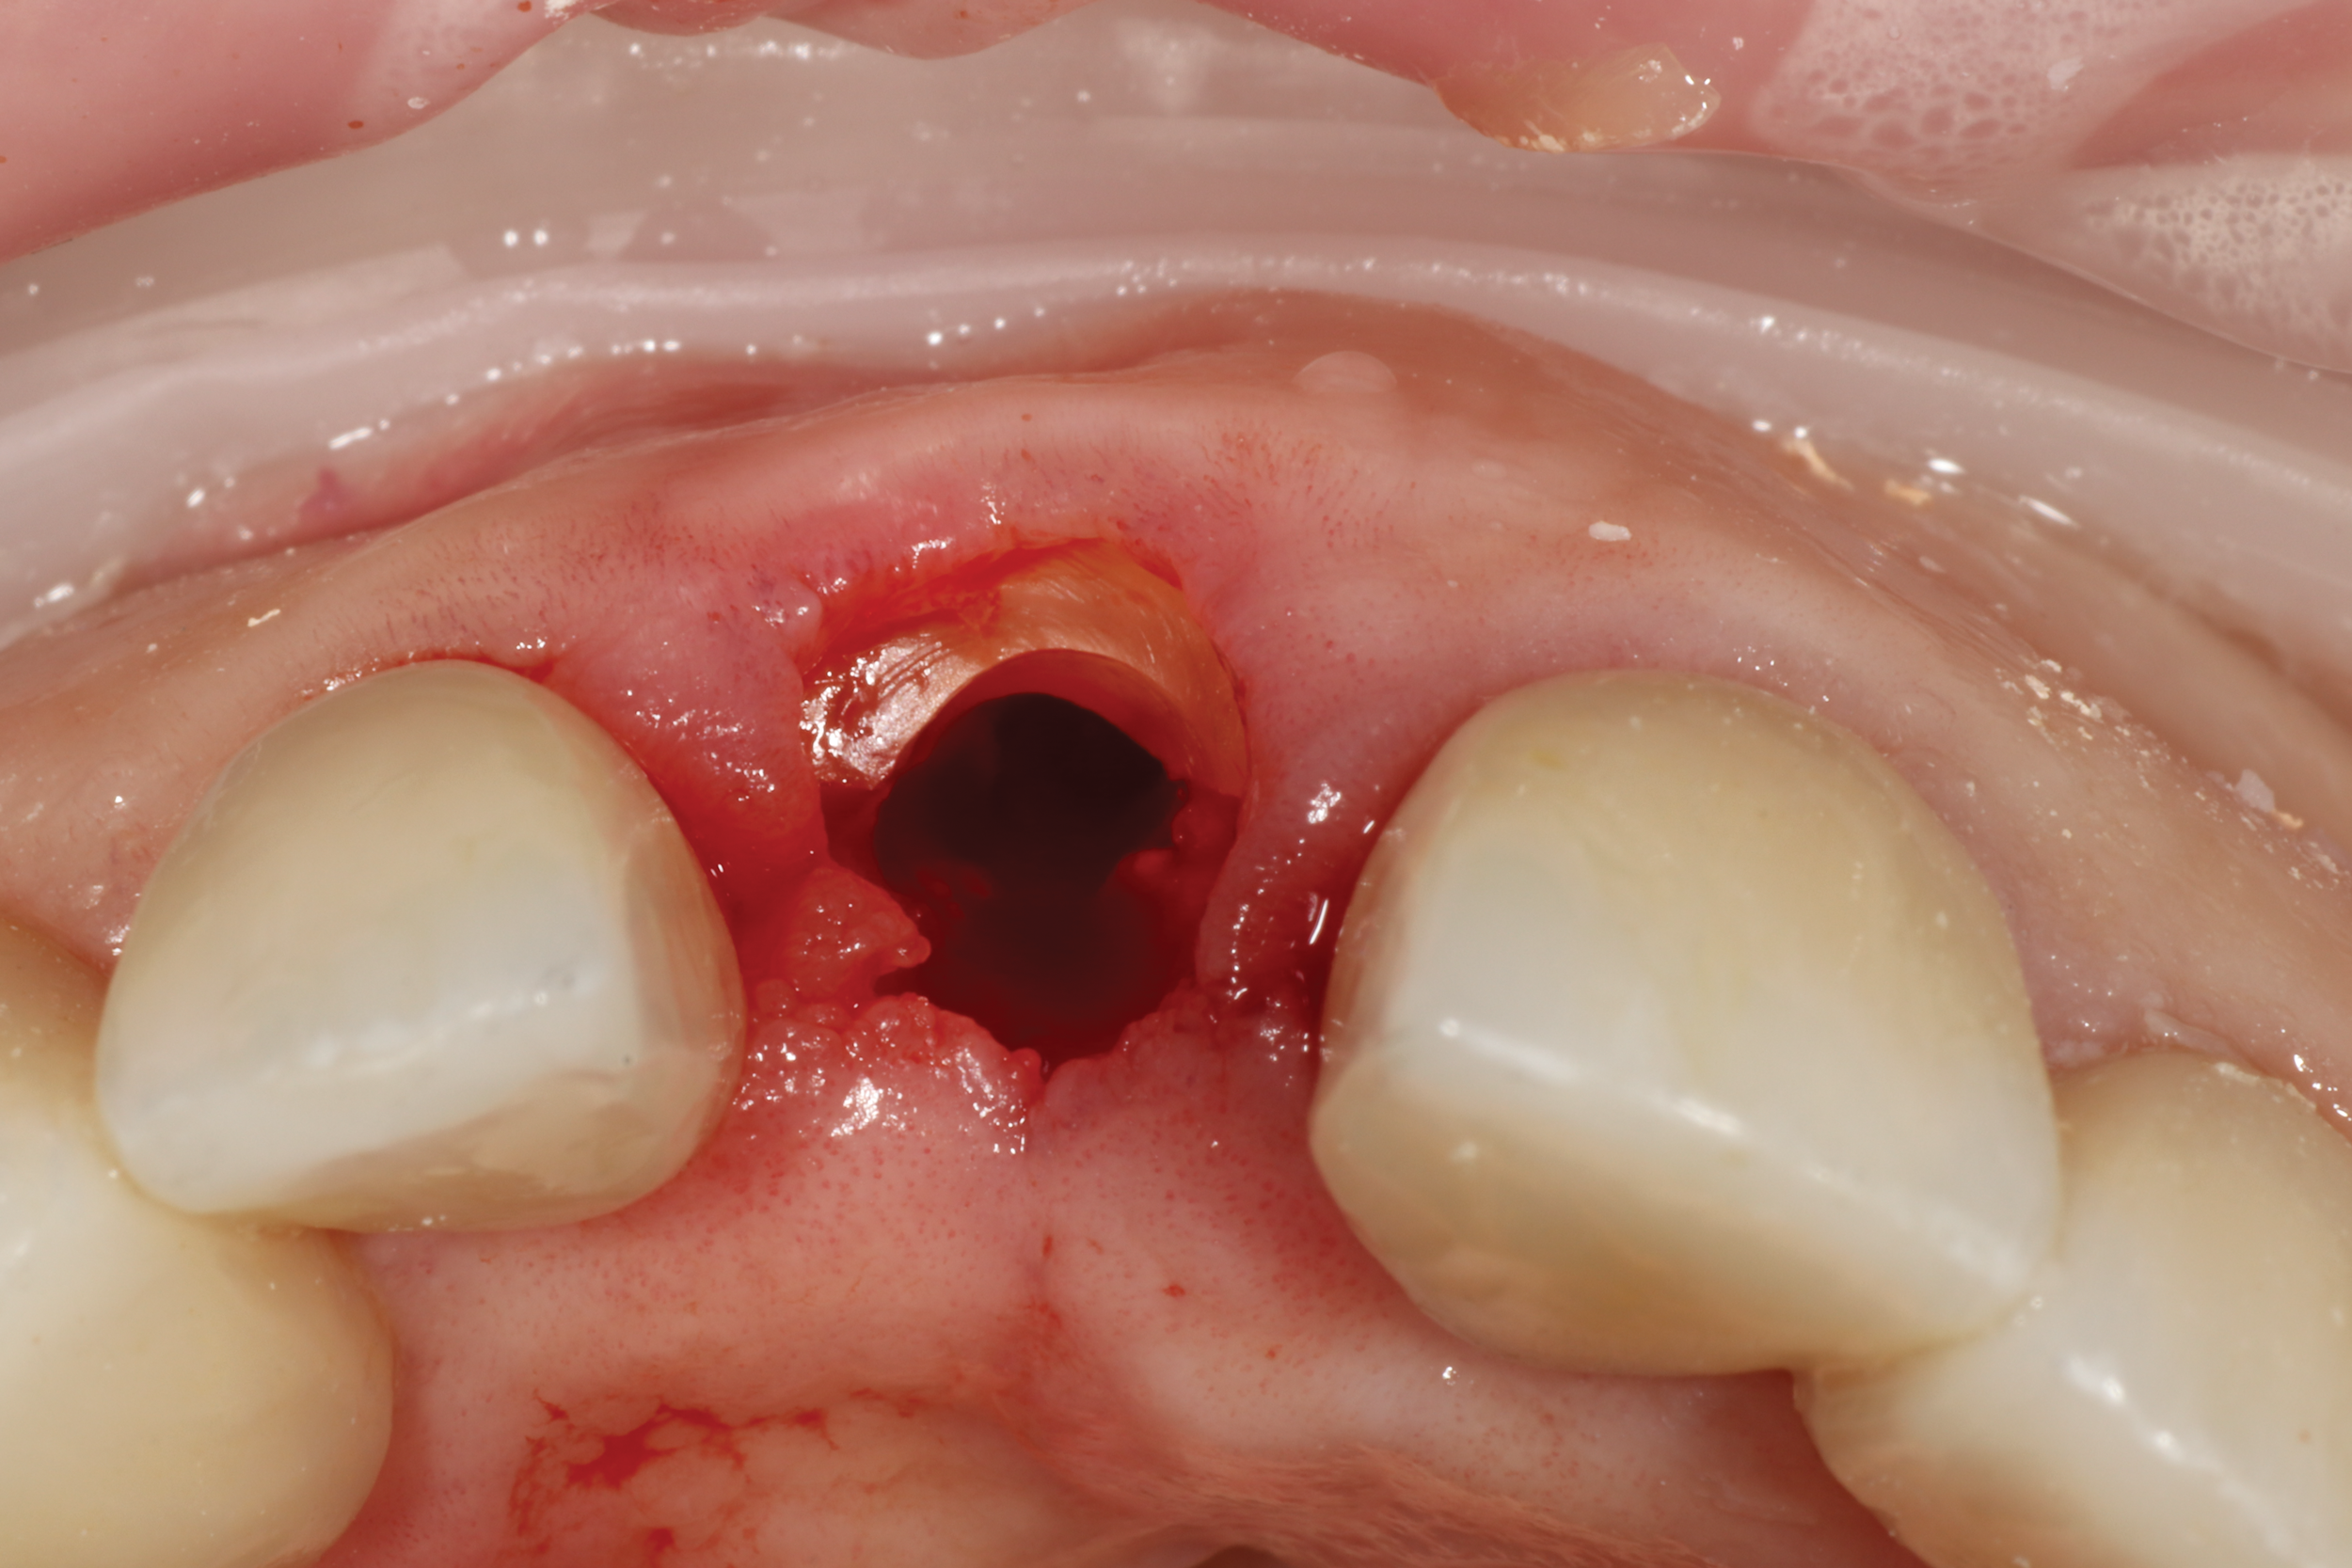

Fig 4. In partial extraction therapy, intentional

sectioning of a root leaves a fragment attached to the facial aspect to

preserve hard and soft tissue. An implant can be placed simultaneously

or in a delayed approach.

Figure 4

Dynamic navigation is not limited to the drilling of implant osteotomies. Surgical devices, such as piezo surgical units, can be used for sinus window access, bone plate harvesting, ridge splitting, bone reduction, and more. High-speed and low-speed handpieces, as well as subsequent drills, can be calibrated and used to plan specific surgical procedures, such as partial extraction therapy (Figure 4),8 a technique that involves retaining a fragment of tooth while preserving the remaining alveolar bone following tooth extraction.9,10